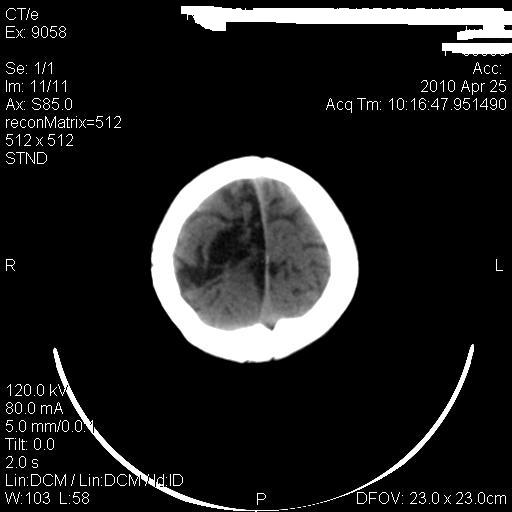

标题: PED3218:3岁女孩,曾有外伤史。未提供前片 [打印本页]

标题: PED3218:3岁女孩,曾有外伤史。未提供前片

发育略有障碍。欢迎大家发言。谢谢!

考虑右侧额顶叶脑软化灶并脑穿通畸形。

考虑:1)右侧额顶叶脑软化灶并脑穿通畸形。2)胼胝体发育不良。

支持考虑:1)右侧额顶叶脑软化灶并脑穿通畸形。2)胼胝体发育不良。

1)右侧额顶叶脑软化灶。2)胼胝体发育不良?

考虑右侧额顶叶软化灶并脑穿通畸形,胼胝体发育不全。

还有脑室周围白质软化症